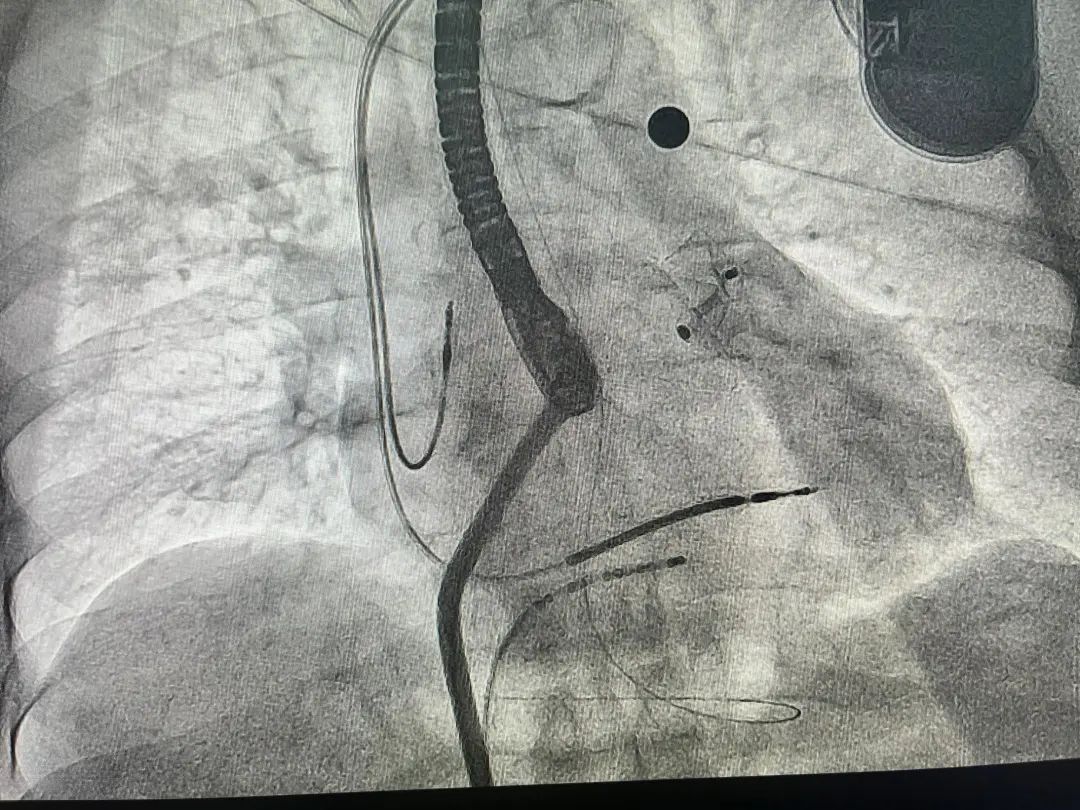

患者全麻后进行左心耳封堵术,在左心耳DSA造影及超声检查下,观察左心耳为菜花型,开口约23mm,锚定区约22mm,选择25mm(固定盘25mm/封堵盘32mm) Amulet左心耳封堵器。

食道超声评估左心耳封堵完全,牵拉稳定,无残余分流,完美释放。手术非常成功。